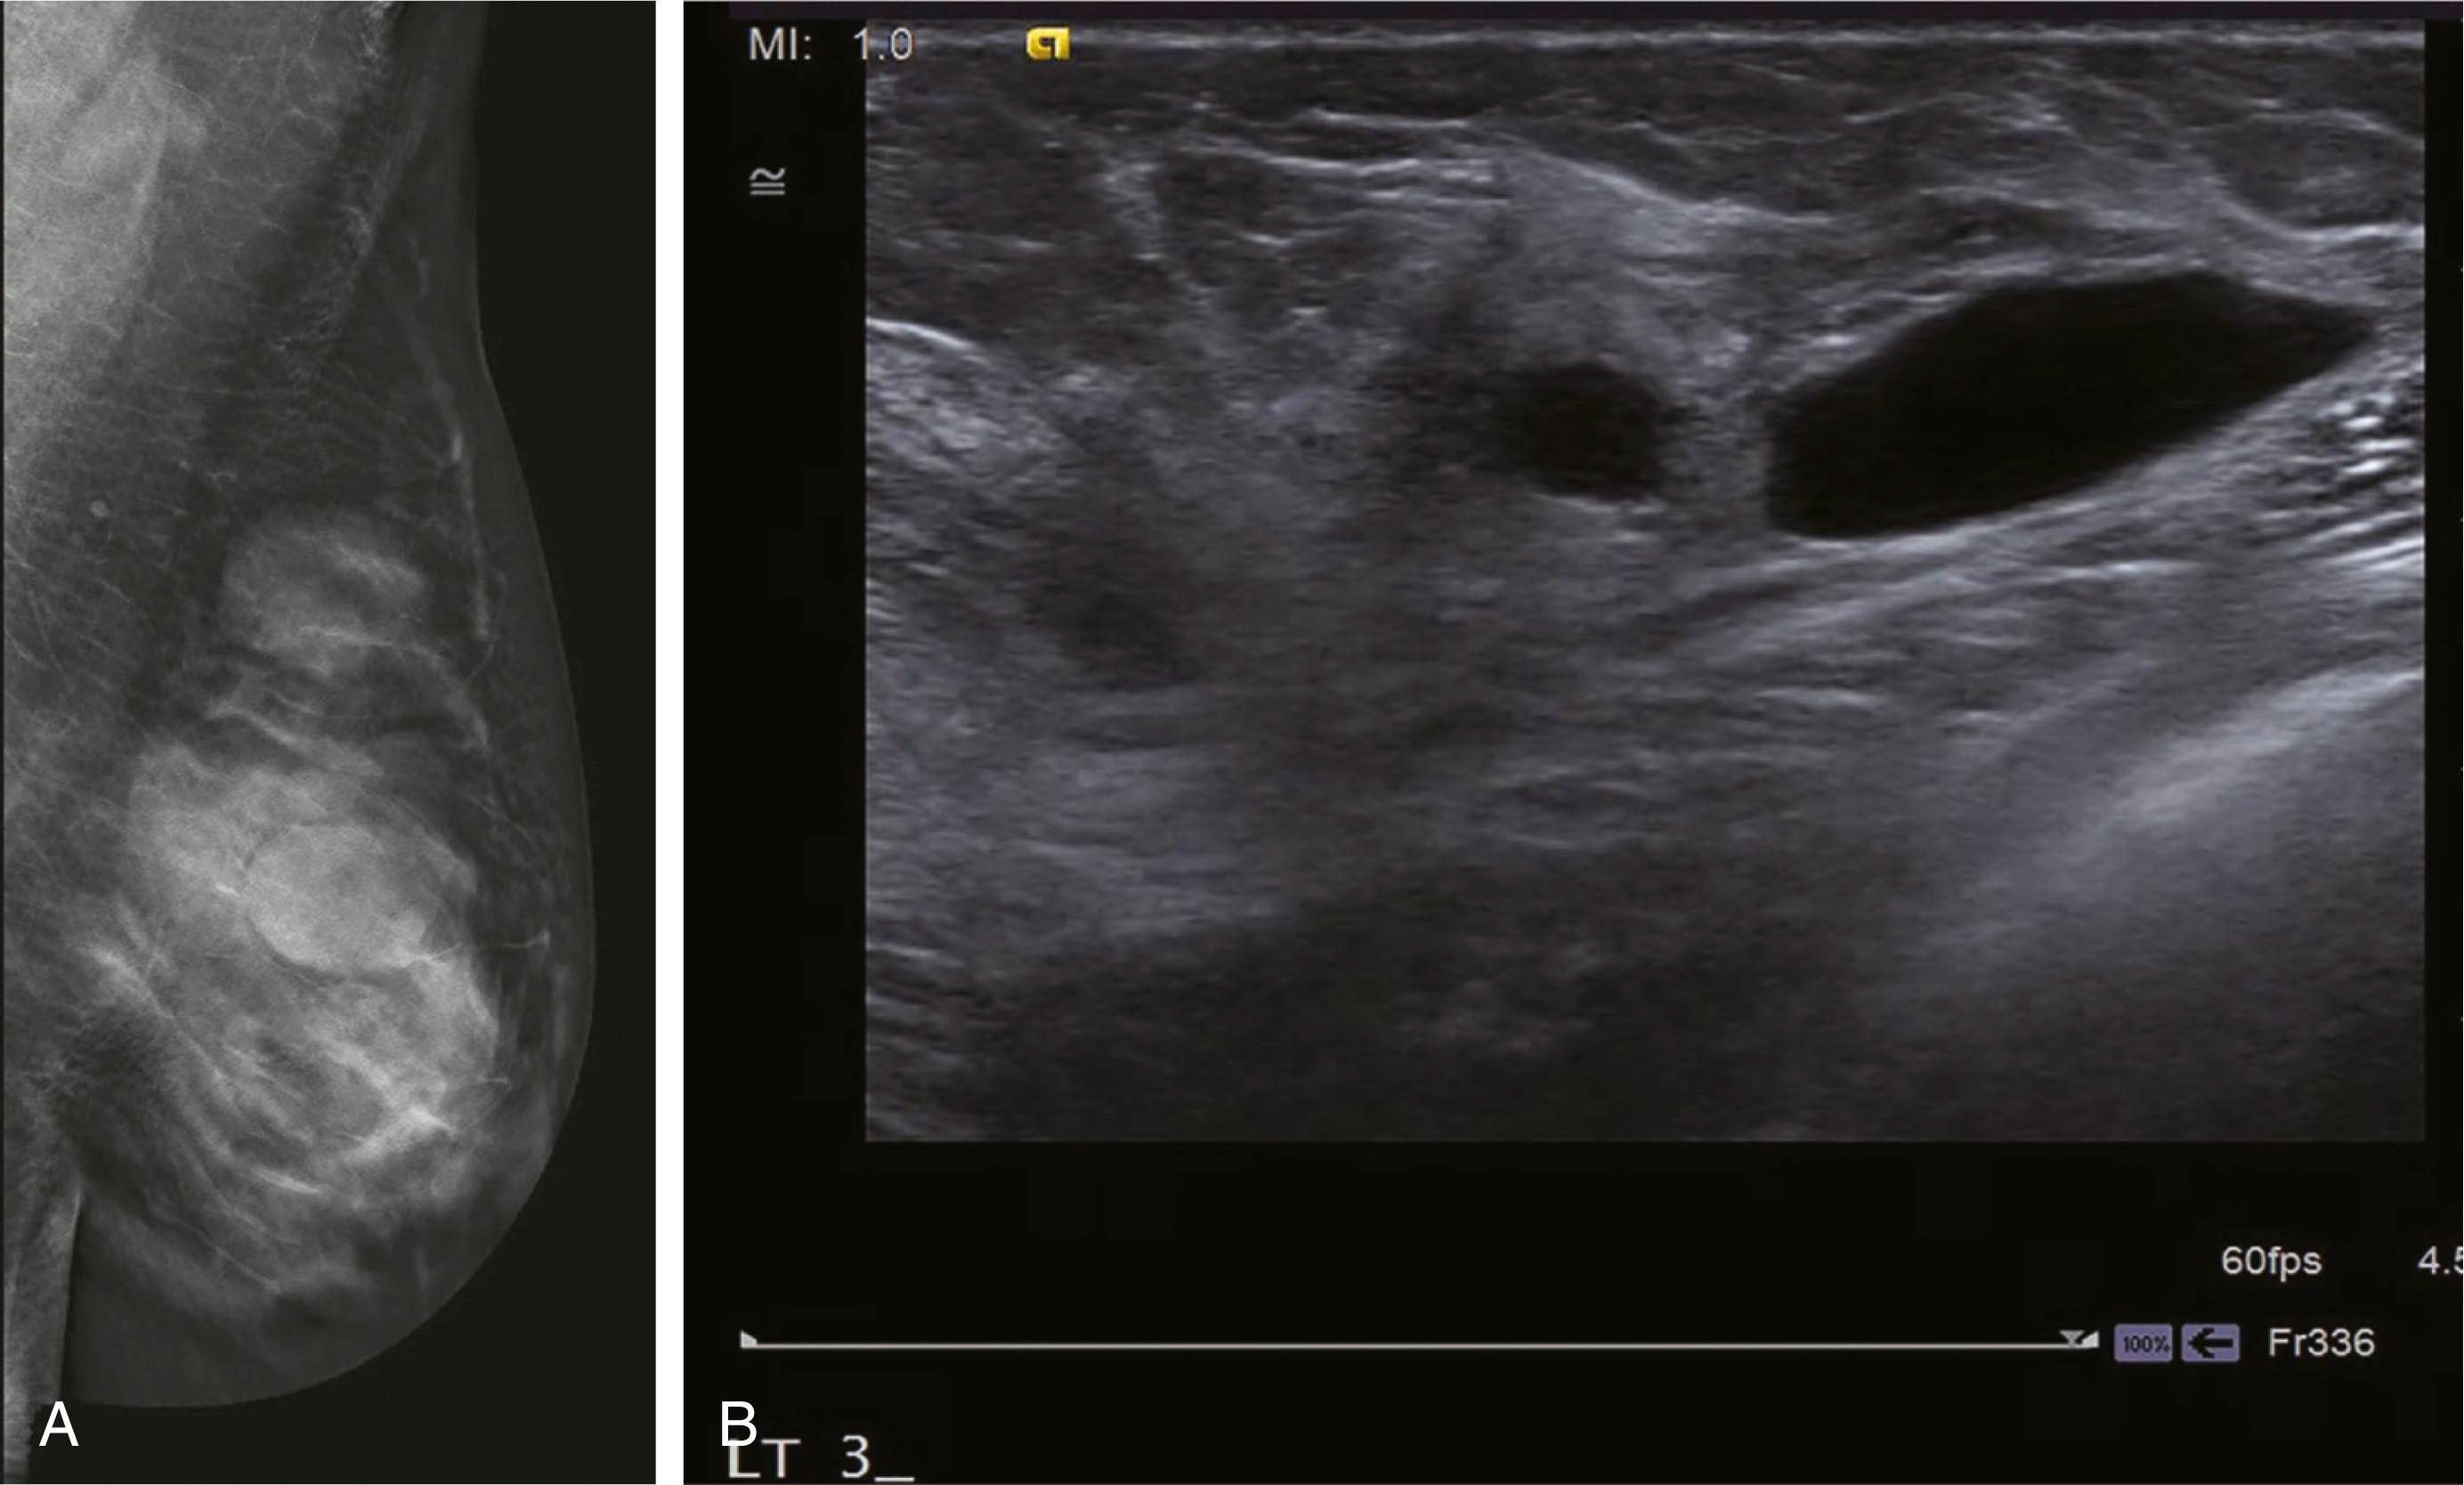

Benign masses

Cysts are typically oval or round, with a distinct border and low density. US will confirm the presence of a fluid-filled simple cyst ( Fig. 12.6 ).

Fig. 12.6, (A) Tomosynthesis mediolateral oblique view demonstrating multiple round masses, most likely benign. (B) Ultrasound image of the same patient demonstrating simple cysts.